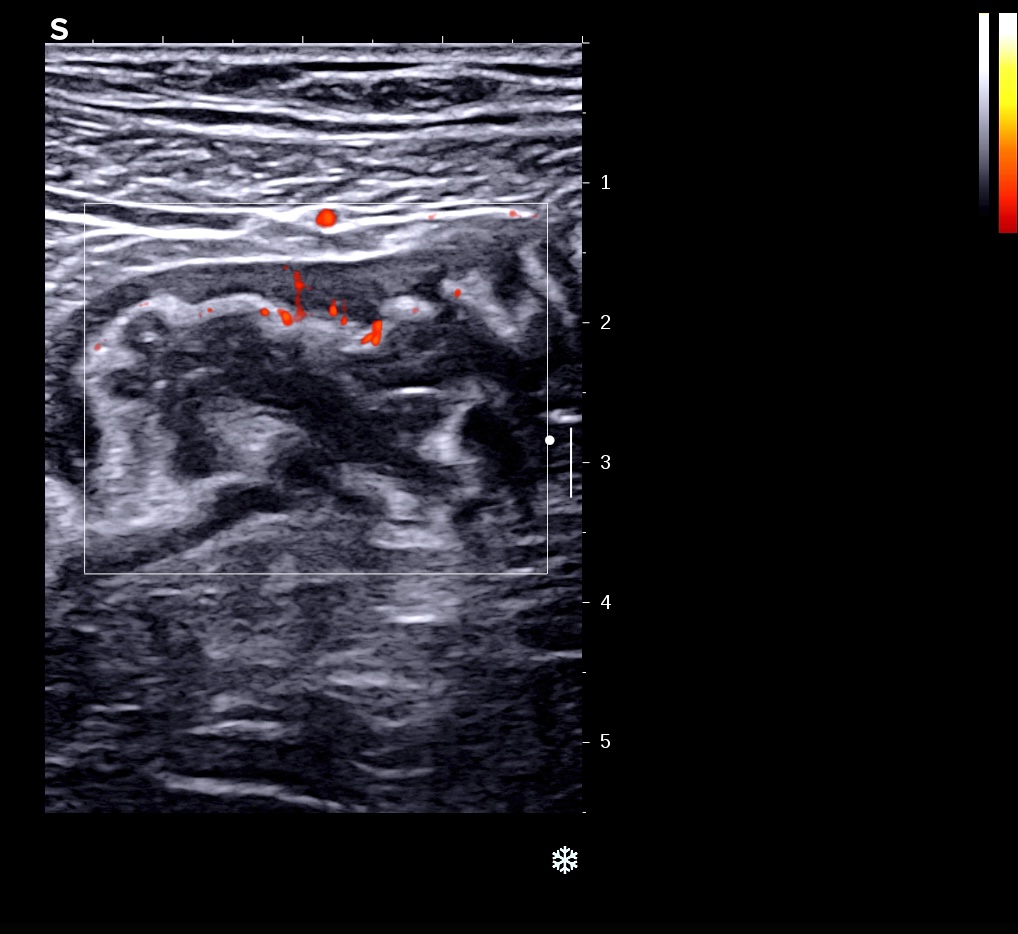

Colon hypoéchogène paroi irrégulière à l'extérieure, l'inflammation est transmurale